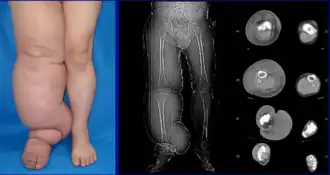

Lymphedema seen on CT scan

The most common manifestation of lymphedema is soft tissue swelling (edema). As the disorder progresses, worsening edema and skin changes including discoloration, verrucous (wart-like) hyperplasia, hyperkeratosis, papillomatosis, dermal thickening, and ulcers may be seen. Additionally, there is increased risk of infection of the skin, known as erysipelas.